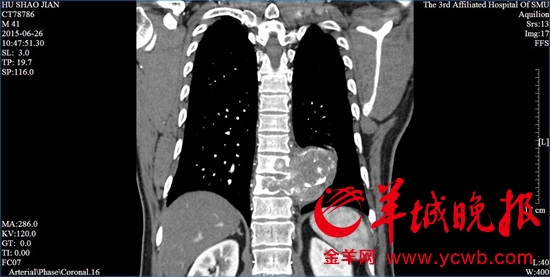

一位患者的脊柱已被腫瘤包圍。(圖片來源:金羊網(wǎng))